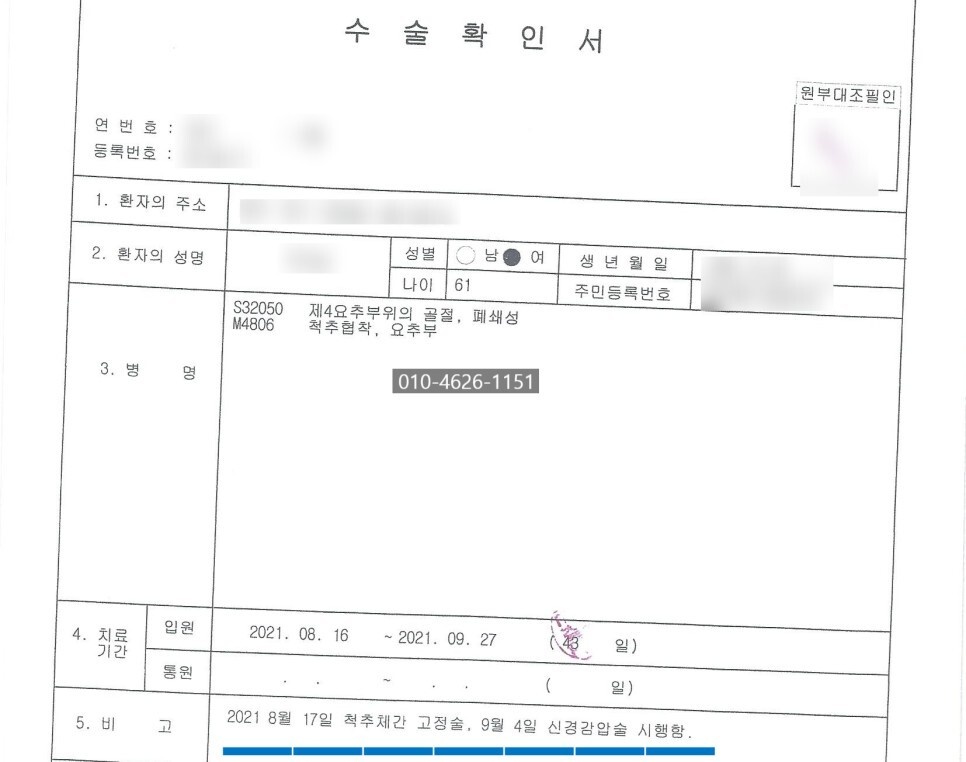

오늘은 넘어지는 사고로 요추 4번

압박골절 되어 척추성형술 시행하였으나,

요추3-4-5번 고정술 시행한 분에 대한

병원 의무기록 및 사고내용 검토결과,

침대에서 낙상 후 허리통증 발현하여

요추4번 압박골절 진단 받았고,

이후 1차 수술로 척추체성형술 시행하였으나,

신경증상 호전이 되지 않아 2차 수술로

요추 3-4-5번 유합술 하였으나,

신경증상 또 발생하여 3차 수술로

신경감압술 시행하였습니다.